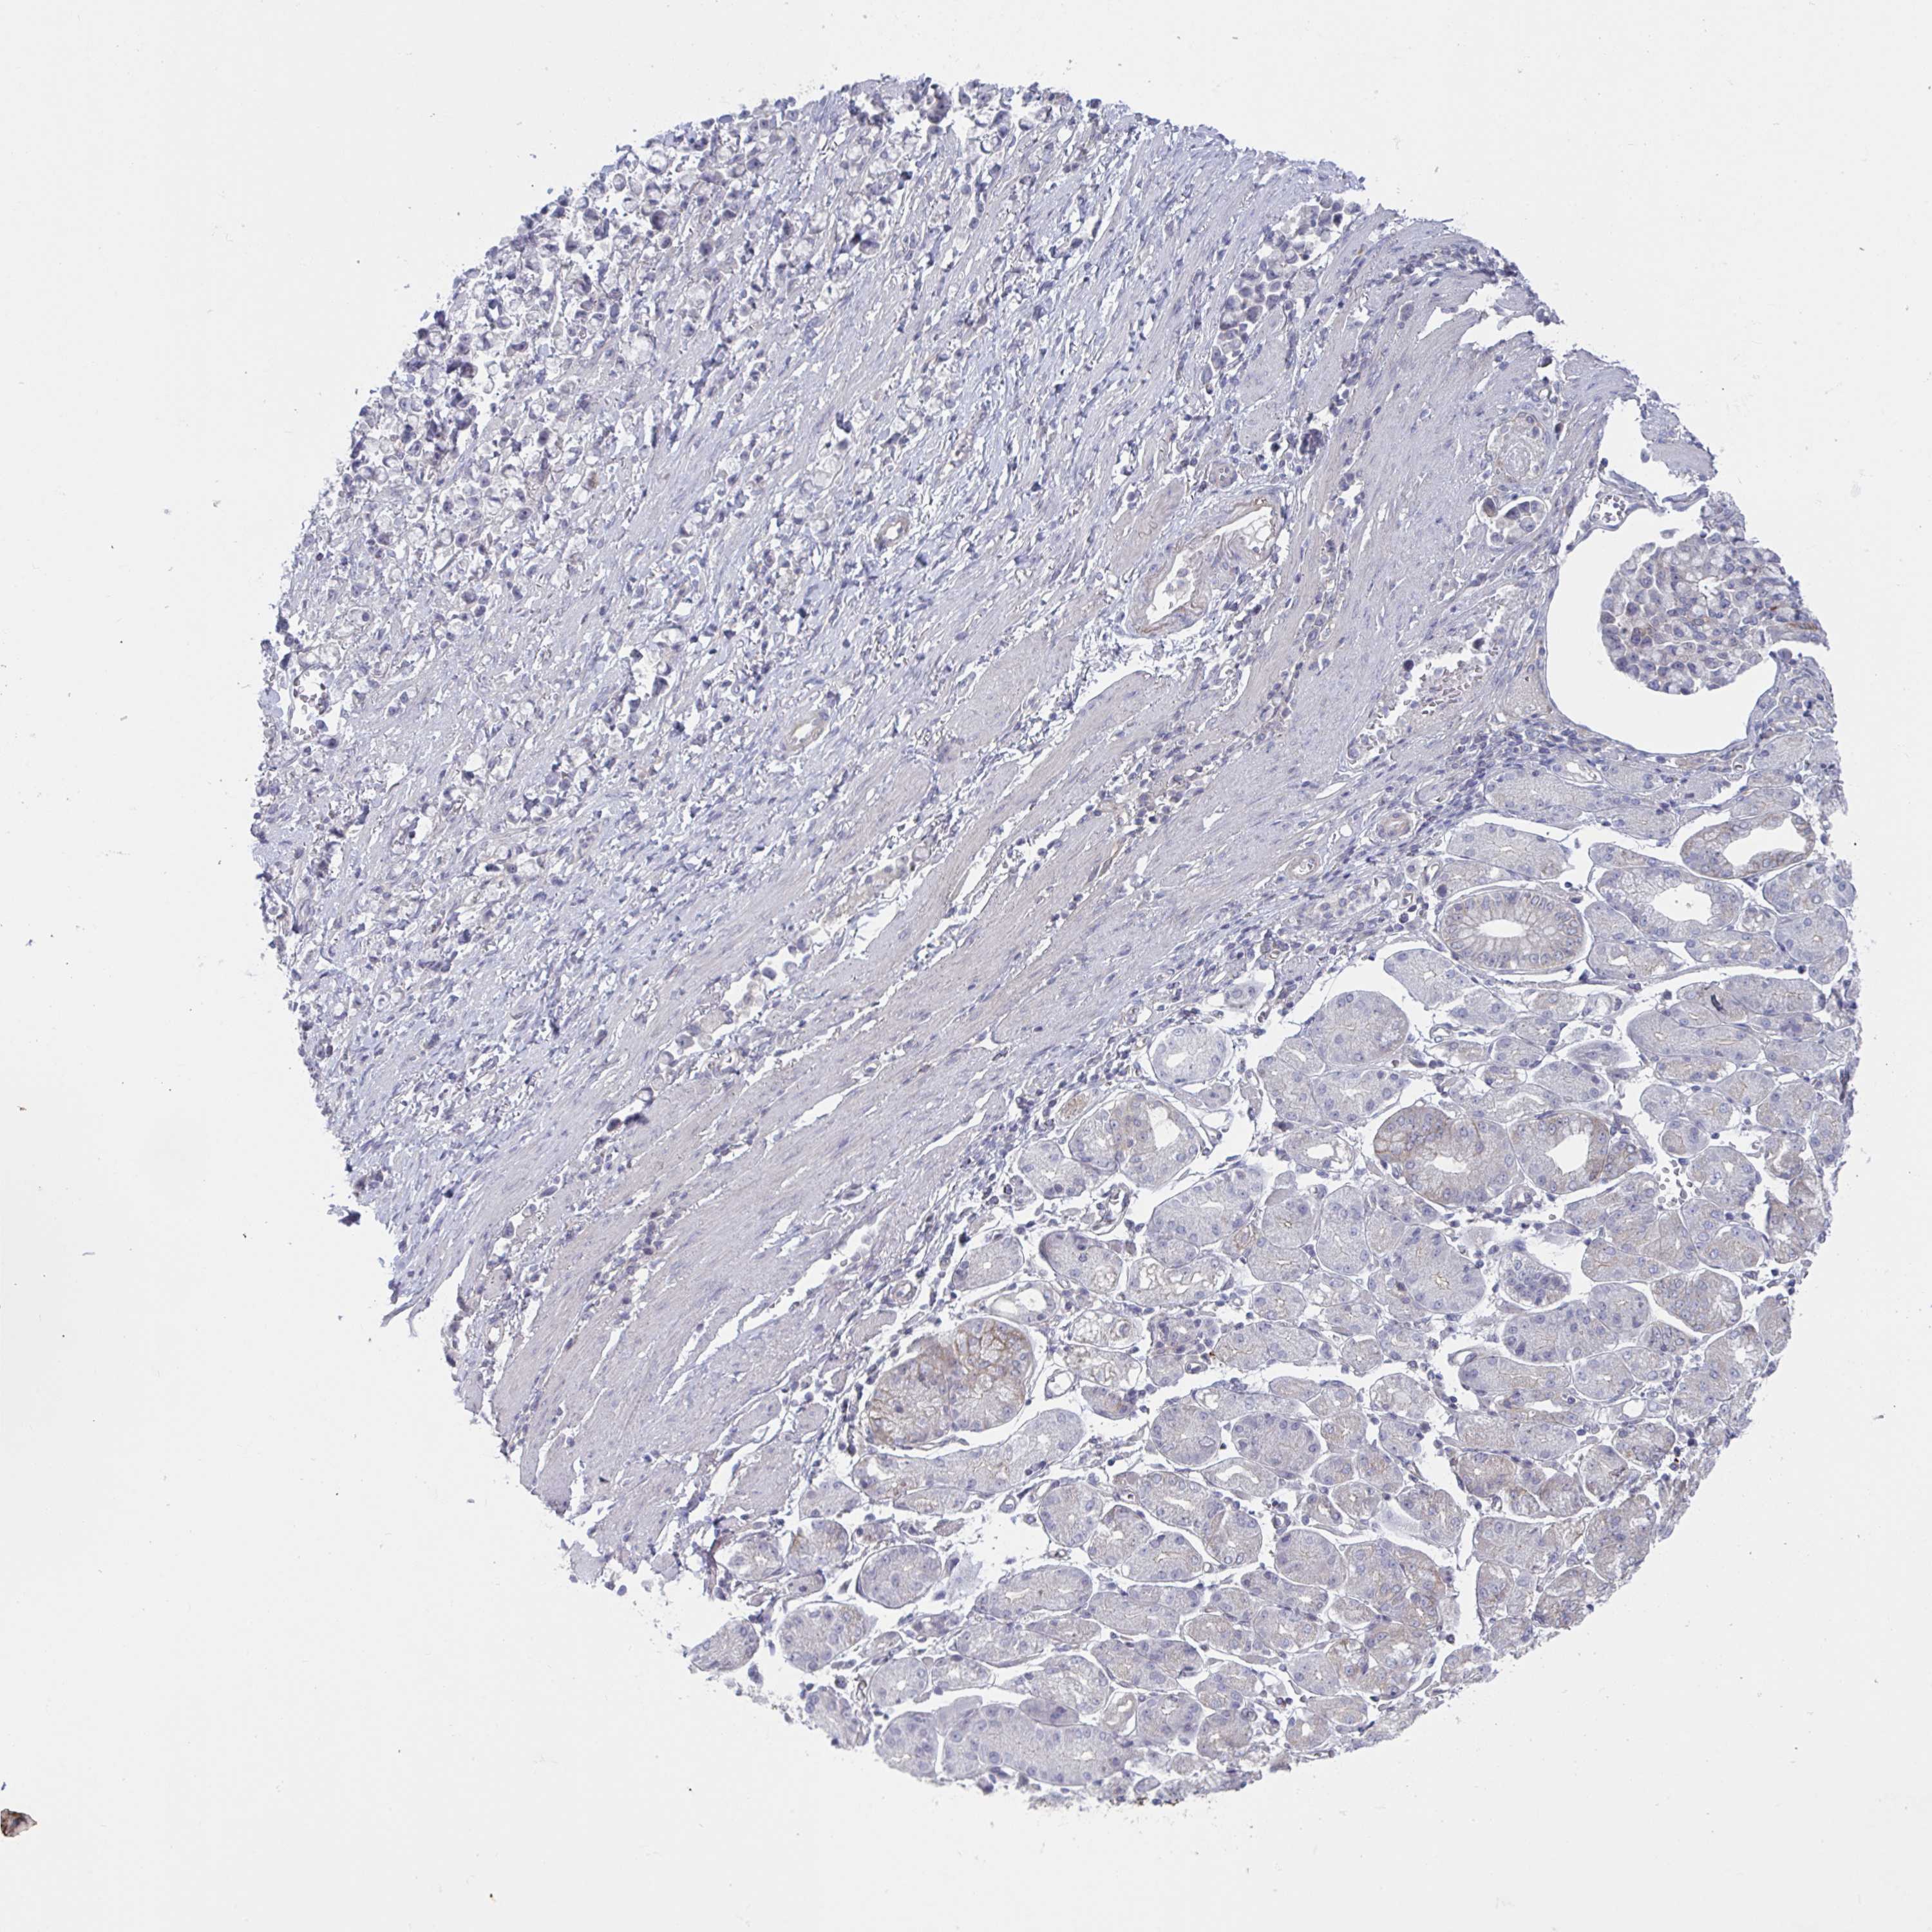

STOMACH CANCER - Protein expressioni

A mouse-over function shows sample information and annotation data. Click on an image to view it in a full screen mode. Samples can be filtered based on level of antibody staining by selecting one or several of the following categories: high, medium, low and not detected. The assay and annotation is described here.

Antibody stainingi

Antibody staining in the annotated cell types in the current human tissue is reported as not detected, low, medium, or high, based on conventional immunohistochemistry profiling in selected tissues. This score is based on the combination of the staining intensity and fraction of stained cells.

Each image is clickable and will lead to virtual microscopy that enables deeper exploration of all samples and also displays staining intensity scores, fraction scores and subcellular localization as well as patient and tissue information for each sample.

Antibody HPA059921

Staining

High

Medium

Low

Not detected

Intensity

Strong

Moderate

Weak

Negative

Quantity

>75%

75%-25%

<25%

None

Location

Nuclear

Cytoplasmic/membranous

Cytoplasmic/membranous,nuclear

Adenocarcinoma, NOS